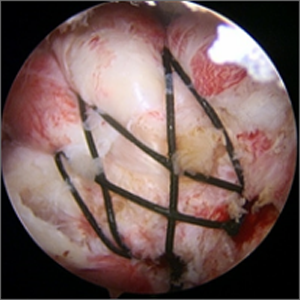

整形外科における手術の役割 肩腱板断裂治療のアルゴリズム 不全断裂 小断裂 中~大断裂 一次修復不能広汎性断裂 保存療法(リハビリ:運動療法/物理療法) 手術療法 関節鏡下腱板修復術 腱移行術、腱移植術、リバース型人工関節 腱板断裂の治療の基本は保存療法ですが、それが反応しない場合には、関節鏡下腱板修復術が適応されます。 修復前 修復後 関節鏡下腱板修復術は「肩に小さな穴を数か所開け、関節鏡で中をのぞきながら縫い合わせる方法」で、私の得意分野です。 不全断裂 小断裂 中~大断裂 一次修復不能広汎性断裂 保存療法(リハビリ:運動療法/物理療法) 手術療法 関節鏡下腱板修復術 腱移行術、腱移植術、リバース型人工関節 縫いきれないほどの大きな断裂には、腱の移植や人工関節が必要になります。 手術を望まない方へは、間葉系幹細胞を用いた再生医療の提供に取り組んでいます。